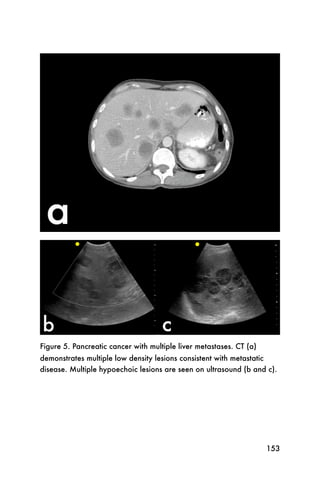

A pericardial effusion will appear as an echo-lucent

(black) area between the heart and the thin white stripe

of the pericardium, as shown in Figure 16.

Figure 16. Subxyphoid view showing a pericardial effusion

As mentioned, if the pericardial effusion has more

inflammatory debris, as in a pericardial effusion related

to tuberculosis, the pericardial effusion may appear

more gray or echo-dense.